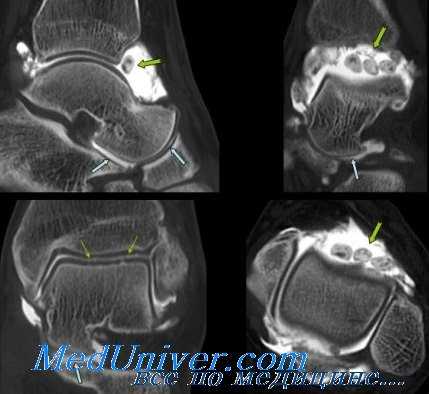

Рентгенография голеностопного сустава

Рентгенографическое исследование голеностопного сустава следует выполнять во всех случаях, кроме явного повреждения I степени. Снимки в обычных проекциях могут быть дополнены снимками с нагрузкой, сделанными во время инверсионной нагрузки или проверки симптома переднего выдвинутого ящика голеностопного сустава. У некоторых больных с растяжением II степени можно обнаружить небольшой костный фрагмент возле латеральной лодыжки. Это указывает на неполный отрыв и обычно свидетельствует о повреждении II степени латеральных связок голеностопного сустава, называемом переломорастяжением.